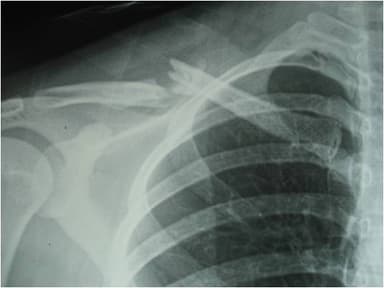

Xương đòn hay xương quai xanh là xương ở phần vai và ngực cấu thành, có vai trò trong sức mạnh vai – cánh tay và yếu tố thẩm mỹ. Gãy xương đòn là tình trạng chấn thương ở bộ phận này và thường gặp với đoạn 1/3 giữa. Những biểu hiện gãy xương đòn bao gồm:

Gãy xương đòn là tình trạng chấn thương ở bộ phận này và thường gặp với đoạn 1/3 giữa

Phẫu thuật gãy xương đòn là sử dụng các phương tiện để nối phần xương đã gãy về tình trạng ban đầu tạo điều kiện cho xương hồi phục. Phương pháp này áp dụng cho bệnh nhân với đường gãy quá mức phức tạp, gãy dài hoặc di lệch nhiều chồng ngắn trên 2cm đe dọa tổn thương mạch máu.